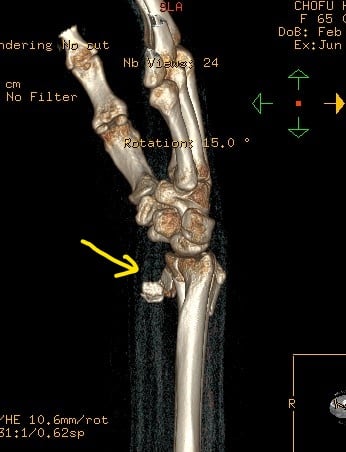

〇前腕骨遠位端骨折

当症例も手術の日程が決まっていましたがインターネットで当院を知り遠くから相談に来らました。

レントゲンとCTを見させてもらいましたが、骨折に伴い第三骨片がはみ出しています。

患者さんンは全身麻酔に抵抗があり、どうしても避けたいとのことでした。

当院で治療するとなると、当初は毎日来院していただき固定を

確認 血行障害を防ぎ 患部の清拭 超音波治療 動かせる指の

運動療法を行います。

ご住所をお聞きしたところに私の信頼する先生のご近所だったので、保存療法を希望している旨をお伝えして経過観察をお願いしました。

2か月経過したころ当院に戻られ今後のマッサージ リハビリを希望されました。

手術はしませんでしたが経過は良好です。